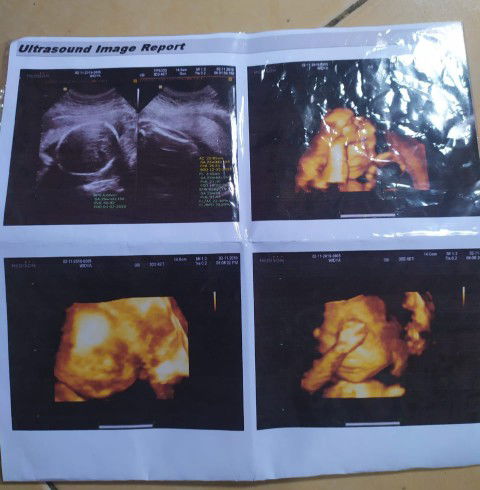

HASIL USG

Halooo bunda bunda Ini babyM usia 25w2d, masih malu malu nunjukin mukanya? kepalanya udah dibawah mudah2an ga muter2 lagi. Tapi alhamdulillah dd ga pelit kasih tau jenis kelaminnya hihi Boleh di share bun hasil usg dd nya donggg?❤

HPL Februari

Buibuuu disini ada yang HPL Februari? Ini pas USG 11w 2d, besok aku 16week bun. Kira2 kalo 16w USG udah keliatan JK belum ya bun, terus bagusnya USG apa biar dd nya keliatan jelas?? Ada yg pernah USG lewat vagina ? Gimana sih rasanya bun, masih tanya pengalaman dulu kalo misal bagus mau nyoba hehe Mohon pencerahannya